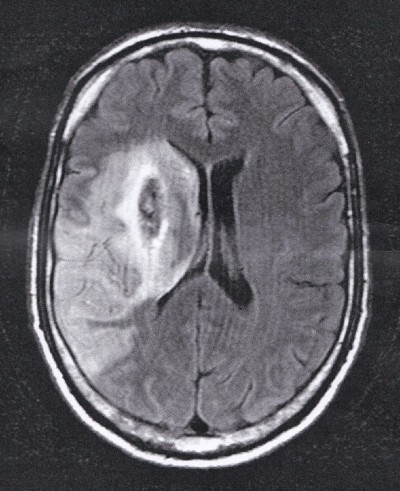

TIA - STROKE - Schlaganfall

CDK Doppler Klinik: Juni 2011 - September 2021